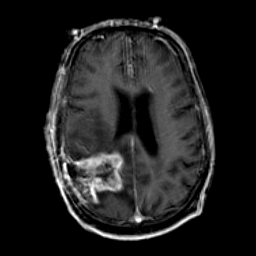

Glioma Overlay -- Slice #13

[Home][Help][Clinical] Slice 13